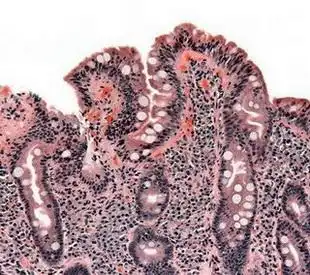

鱼鳞病的最佳治疗时期是什么时候